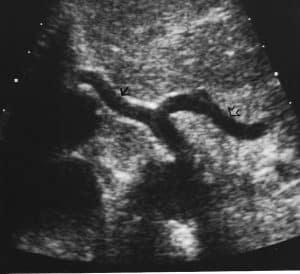

Master the art of abdominal duplex anatomy with this detailed guide, covering visceral and vascular landmarks, sonographic techniques, and Doppler essentials. Discover how to optimize ultrasound imaging, identify key arteries and veins, and correlate anatomy for accurate diagnoses and effective patient care.

Describe the visceral and vascular sonographic anatomy of the abdomen

Relate the vascular anatomic landmarks used for ultrasound interrogation of the central and upper abdomen

Define the most common mesenteric, renal, and hepatic anatomic anomalies

Discuss the optimal image planes employed for sonographic imaging of the mesenteric, renal, and hepato-portal vessels